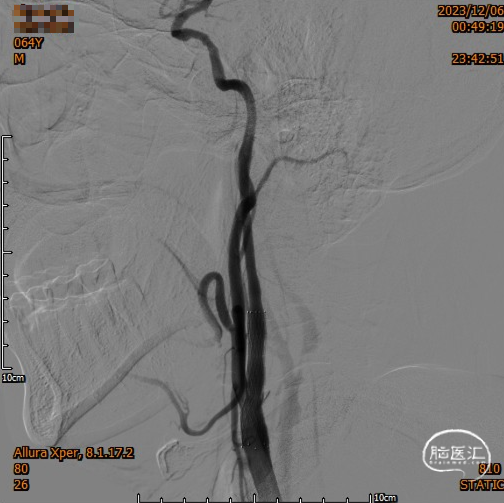

头颈部CTA

DSA

造影,颈内动脉未见血栓,颅内动脉较前未见明显减少,无明显血栓逃逸。

复查造影支架成形良好,颅内较前无明显改变,未发现血管减少影像,供血较前明显改善。